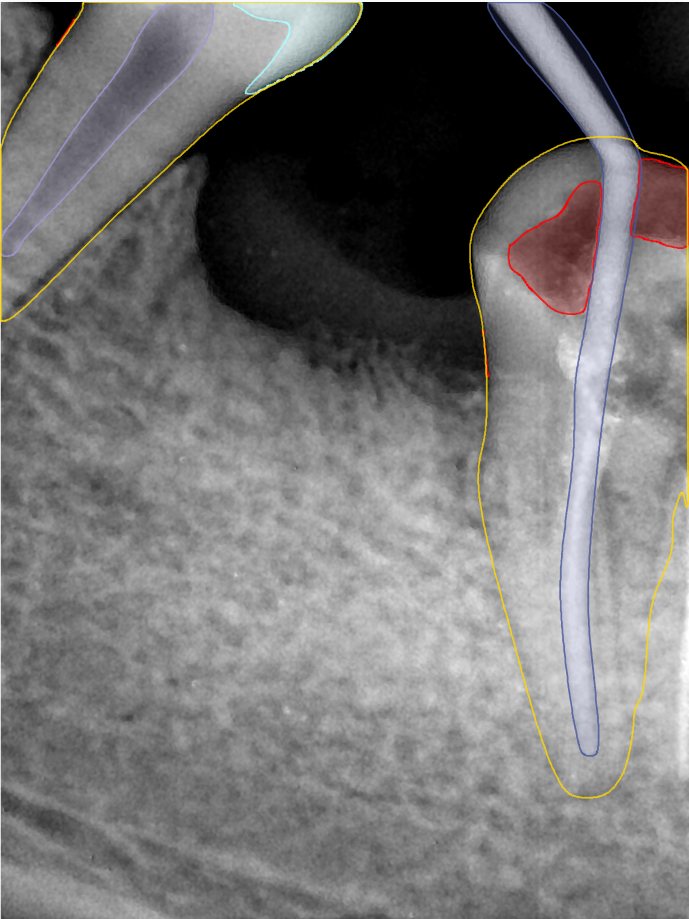

第二版算法问题测试

Updated: 2026-04-13(更新日期)

| 第一版 | 第二版 | 是否解决 | |

|---|---|---|---|

![]() | ![]() ![]() 边角识别有问题 龋齿识别不全 牙髓识别不全 | ![]() | 解决 |

![]() | ![]() 边角识别有问题 识别信息有误 自查(牙冠识别不全) | ![]() | 解决 |

![]() | ![]() ![]() 边角识别有误 大范围填充识别遗漏 | ![]() | 解决 |

![]() | ![]() 识别信息不全 | ![]() | 解决 |

![]() | ![]() ![]() 边角问题 牙胶识别不全 牙冠识别不全 | ![]() | 解决 |

![]() 换图片 | ![]() | ![]() 牙冠部分稍微白了一些就识别成小范围修补,部分判断异常 | 部分解决,修复类略敏感,牙冠部分稍微白了一些就识别成小范围修补,部分判断异常。 |

![]() | ![]() ![]() 牙冠识别不全 牙髓不全 根尖炎龋齿识别有误 | ![]() | 解决 |

![]() | ![]() | ![]() | 解决 |

![]() 换图片 | ![]() | ![]() | 解决 |

![]() | ![]() 牙冠识别有误 | ![]() | 解决 |

![]() 换图片 | ![]() ![]() 边角识别有误 | ![]() 修复类敏感 | 部分解决,图像过白,导致修复类判断异常。 |

![]() 换图片 | ![]() 牙冠识别不全 | ![]() 修复类敏感 | 部分解决,图像过白,导致修复类判断异常 |

结论:修复类出现了不鲁棒的情况,后续需要加入轮廓的扩充数据进行增强。